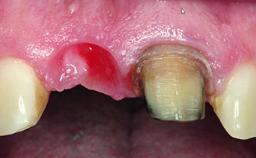

Replacement of an Upper Right Central Incisor with Root Resorption: Ridge Preservation, Early Placement of an RC Bone Level Implant

A 49-year-old female patient was referred for implant therapy to replace the upper right central incisor (tooth 11). The tooth had been assessed by an endodontist who diagnosed a vertical fracture of the root. The tooth had a hopeless prognosis and needed to be extracted. The patient was healthy and was not taking any medications. She was allergic to penicillin. The patient had high esthetic demands but her expectations were realistic. The extraoral examination revealed no facial asymmetries. The right temporomandibular joint demonstrated an opening click but was otherwise asymptomatic. The lip line was high with a significant gingival display.

Placement Protocol Early or late implant placement